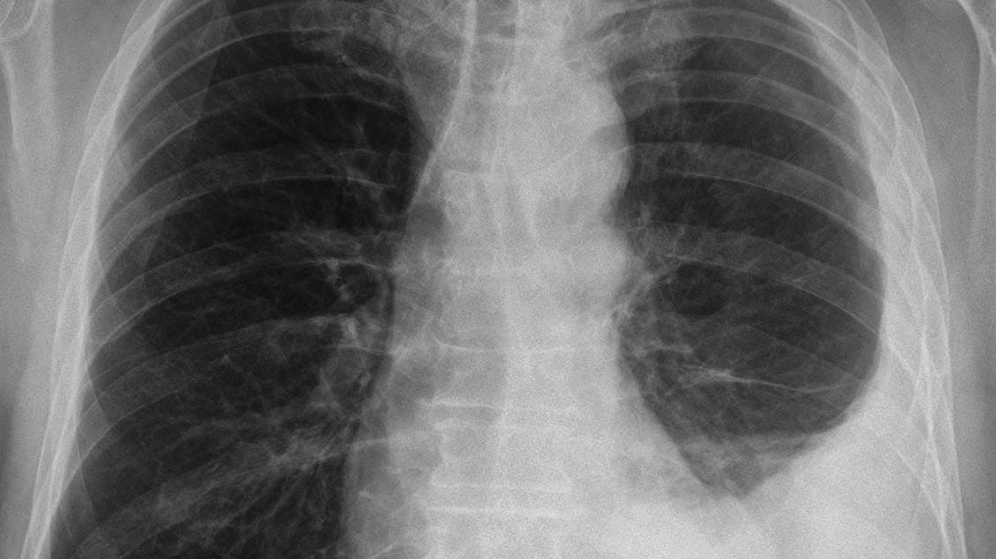

The therapy of pleural mesothelioma requires the interdisciplinary collaboration of oncology, surgery, radio-oncology and pneumology. Therefore, the patient with pleural mesothelioma is best kept in a lung cancer centre, since all specialties are represented here.